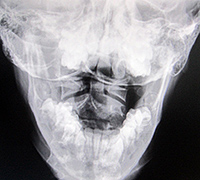

Fig. 3: Lateral Cervical (Normal)

Fig. 4: Lateral Cervical (Abnormal)

Figure 3 represents a normal cervical spine as seen from the lateral view. The lordotic curve provides shock absorption, the disc spaces appear to be full and the cervical gravity line, which is located by a point on the anterior third of the odontoid process then drawing a plumb line straight down, represents the center of gravity of the weight of the head (approximately 10% of body weight). In the optimal state, all bones in the neck should share in the distribution of this weight. In Figure 4, the head is grossly anterior to all of the bones in the cervical spine, the spine is straight and the loading of this neck is highly abnormal.